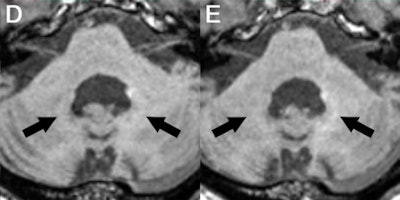

In the current retrospective study, Radbruch and colleagues narrowed their focus to possible evidence of signal intensity on unenhanced T1-weighted MR images in the dentate nucleus of patients who received an average of 23 injections of macrocyclic GBCAs.

A total of 33 patients were studied. All MRI scans were performed exclusively with 3-tesla scanners (Trio, Verio, Prisma, and Skyra, Siemens Healthineers) using the macrocyclic agents gadobutrol (Gadavist, Bayer HealthCare) and gadoterate meglumine (Dotarem, Guerbet). The mean injected dose per MRI scan was 7.74 mmol for gadobutrol and 12.61 mmol for gadoterate meglumine, based on the patient's body weight. There was an average of 12 weeks between every administration.

Signal intensity ratio differences were calculated based on dentate nucleus-to-pons and dentate nucleus-to-middle cerebellar peduncle (MCP) values by subtracting the signal intensity ratio of the first MRI scan from the signal intensity ratio at the last MRI exam. The mean interval between the first and last MRI scans was 273 weeks.

The researchers found no significant T1 signal increase in the dentate nucleus in any of the patients after a mean 23 serial injections of the macrocyclic GBCAs. The findings were reinforced by the dentate nucleus-to-pons ratio of -0.0032 ± 0.0154 (p = 0.248) and the dentate nucleus-to-MCP ratio of -0.0011 ± 0.0093 (p = 0.521).